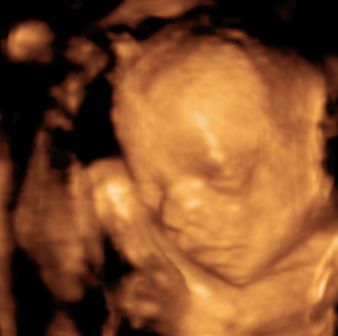

Na, és rakok fel pár képet: Btw: Tiszta apja! :)

Kép Megtalálta az ujját... Kép Cumizik :) Kép Nagyon cumizik :) Bal kezes lesz úgy tűnik. :) Kép Kép Turcsi nózi :)